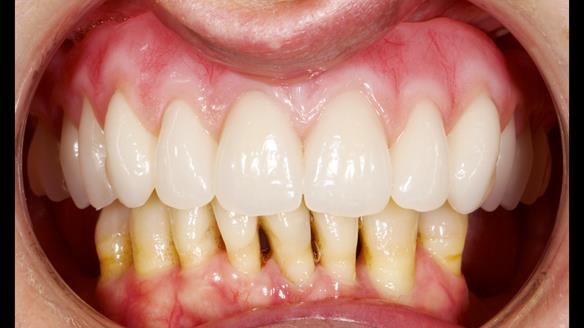

She had previously suffered from generalised periodontitis – stage IV, grade C, currently stable, with reduced attachment across the upper arch.

By the time she came to me, her periodontal condition was stable — but the aesthetics in the upper jaw were very poor.

We provided her with an immediate upper denture (Mk 1), followed by a definitive metal-based upper denture (Mk 2). A lower removable partial denture was discussed, to be made only if needed once the upper treatment was complete. However, at review, this wasn’t necessary — Adnana had excellent neuromuscular control and function, even with a shortened dental arch (SDA).

Rowan, Sam Hesketh and Chris Hesketh provided the stunning technical work. I am very lucky to have them.

- Immediate denture (Mk 1) fitted the same day the teeth came out

- Definitive denture (Mk 2), metal-based and custom-designed for her face

- A restored smile, restored lip support, and a patient who owned the journey